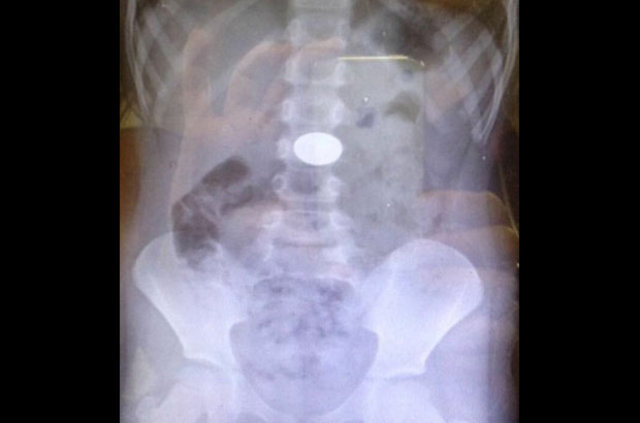

İzmir'deki Tepecik Eğitim ve Araştırma Hastanesi Çocuk Gastroenteroloji Bölümü'nün, yabancı cisim yutan çocukların nefes ve borusu ile midelerinden çıkarttığı, anahtarlık, madeni para, saat pili, ataç, çengelli iğne ve çivi gibi objeler görenleri şaşkına çevirdi.

Çocukların nefes ve borusu ile midelerinden çıkartılan, anahtarlık, madeni para, saat pili, ataç, çengelli iğne ve çivi gibi objeler görenleri şaşkına çevirdi. Anne ve babaların çok dikkatli olması gerektiğini söyleyen Doç. Dr. Maşallah Baran, şöyle dedi:

Genellikle yabancı cisimler 'X' ışınıyla görülebilir. Direk grafi ile metal ve 'X' ışınına duyarlı cisimleri rahatlıkla görebiliyoruz. Ama plastikleri göremiyoruz. Bu durumda oyuncağın bir parçasıyla yutulan parçayı anlamaya çalışıyoruz."

Hastaneye yabancı cisim yutma şikayetiyle getirilen çocuğun ilk etapta takip edildiğini, yaşına ve yuttuğu objenin özelliğine göre de müdahaleye karar verildiğini belirten Dr. Miray Karakoyun, yabancı cisim yutma şikayetiyle başvuran hastalarda, yabancı cismin ne olduğu, çocuğun kaç yaşında olduğu ve yutulan maddenin çekilen filmi sonucu sistemin neresinde olduğunun kendileri için önemli olduğunu kaydederek şöyle dedi:

"Madeni paralar çok sık yutulan cisimler arasında, 4-6 haftaya kadar midede ya da bağırsaktaysa bekleyebiliyoruz ancak yemek borusunda olan vakalarda yutulan yabancı cisim ne olursa olsun endoskopi işlemi yapıyoruz. İkili mıknatıs yutmalarına hemen müdahale ediyoruz. Yoksa ciddi zararlara yol açabiliyor.